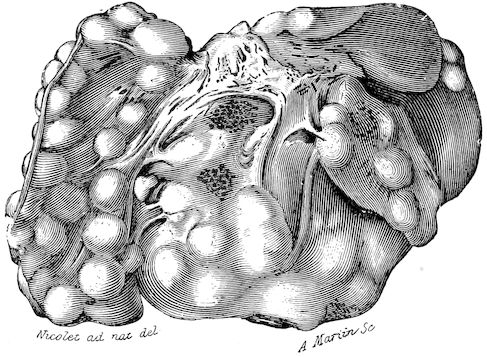

Fig. 1.—Rachitis in a young goat.

Fig. 1.—Rachitis in a young goat.